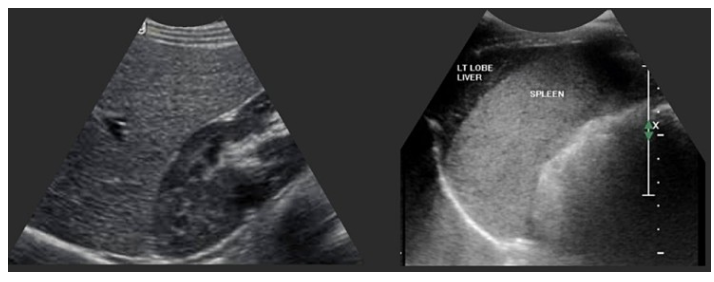

② 정상 liver echotexture는 homogenous echogenicity를 보이며 renal cortex와 비교할 때 약간 echogenicity가 증가되어 보이고 (아래 왼쪽 사진), spleen과 비교할 때 hypoechoic하게 보입니다 (아래 오른쪽 사진).